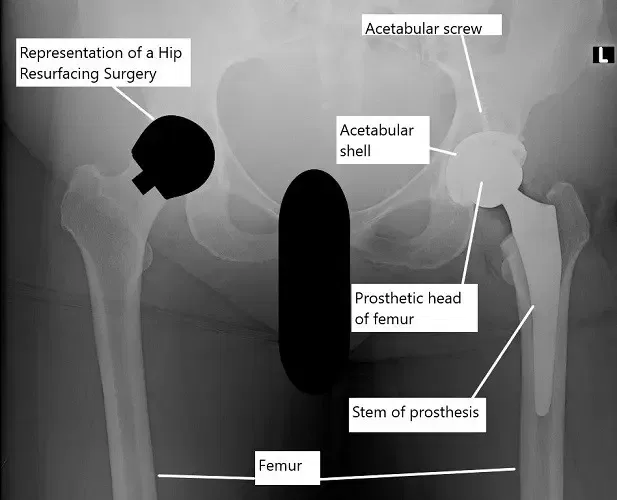

Radiografía que muestra un reemplazo total de cadera en la cadera izquierda y una ilustración de la resurfacing de cadera en la cadera derecha

La cirugía de resurfecemento de cadera es un tipo de prótesis de cadera en la que solo se corta la bola de la cadera enferma y se reemplaza por un implante protésico. La cavidad se reemplaza de forma similar a una prótesis total de cadera.

La articulación de cadera es una articulación de bola y cavidad grande que soporta el peso. La bola (cabeza del fémur) de la articulación está formada por la parte superior del fémur. La bola está unida al cuerpo del fémur a través de un cuello óseo. La bola gira dentro de una cavidad ósea formada por el hueso pélvico (acetábulo).